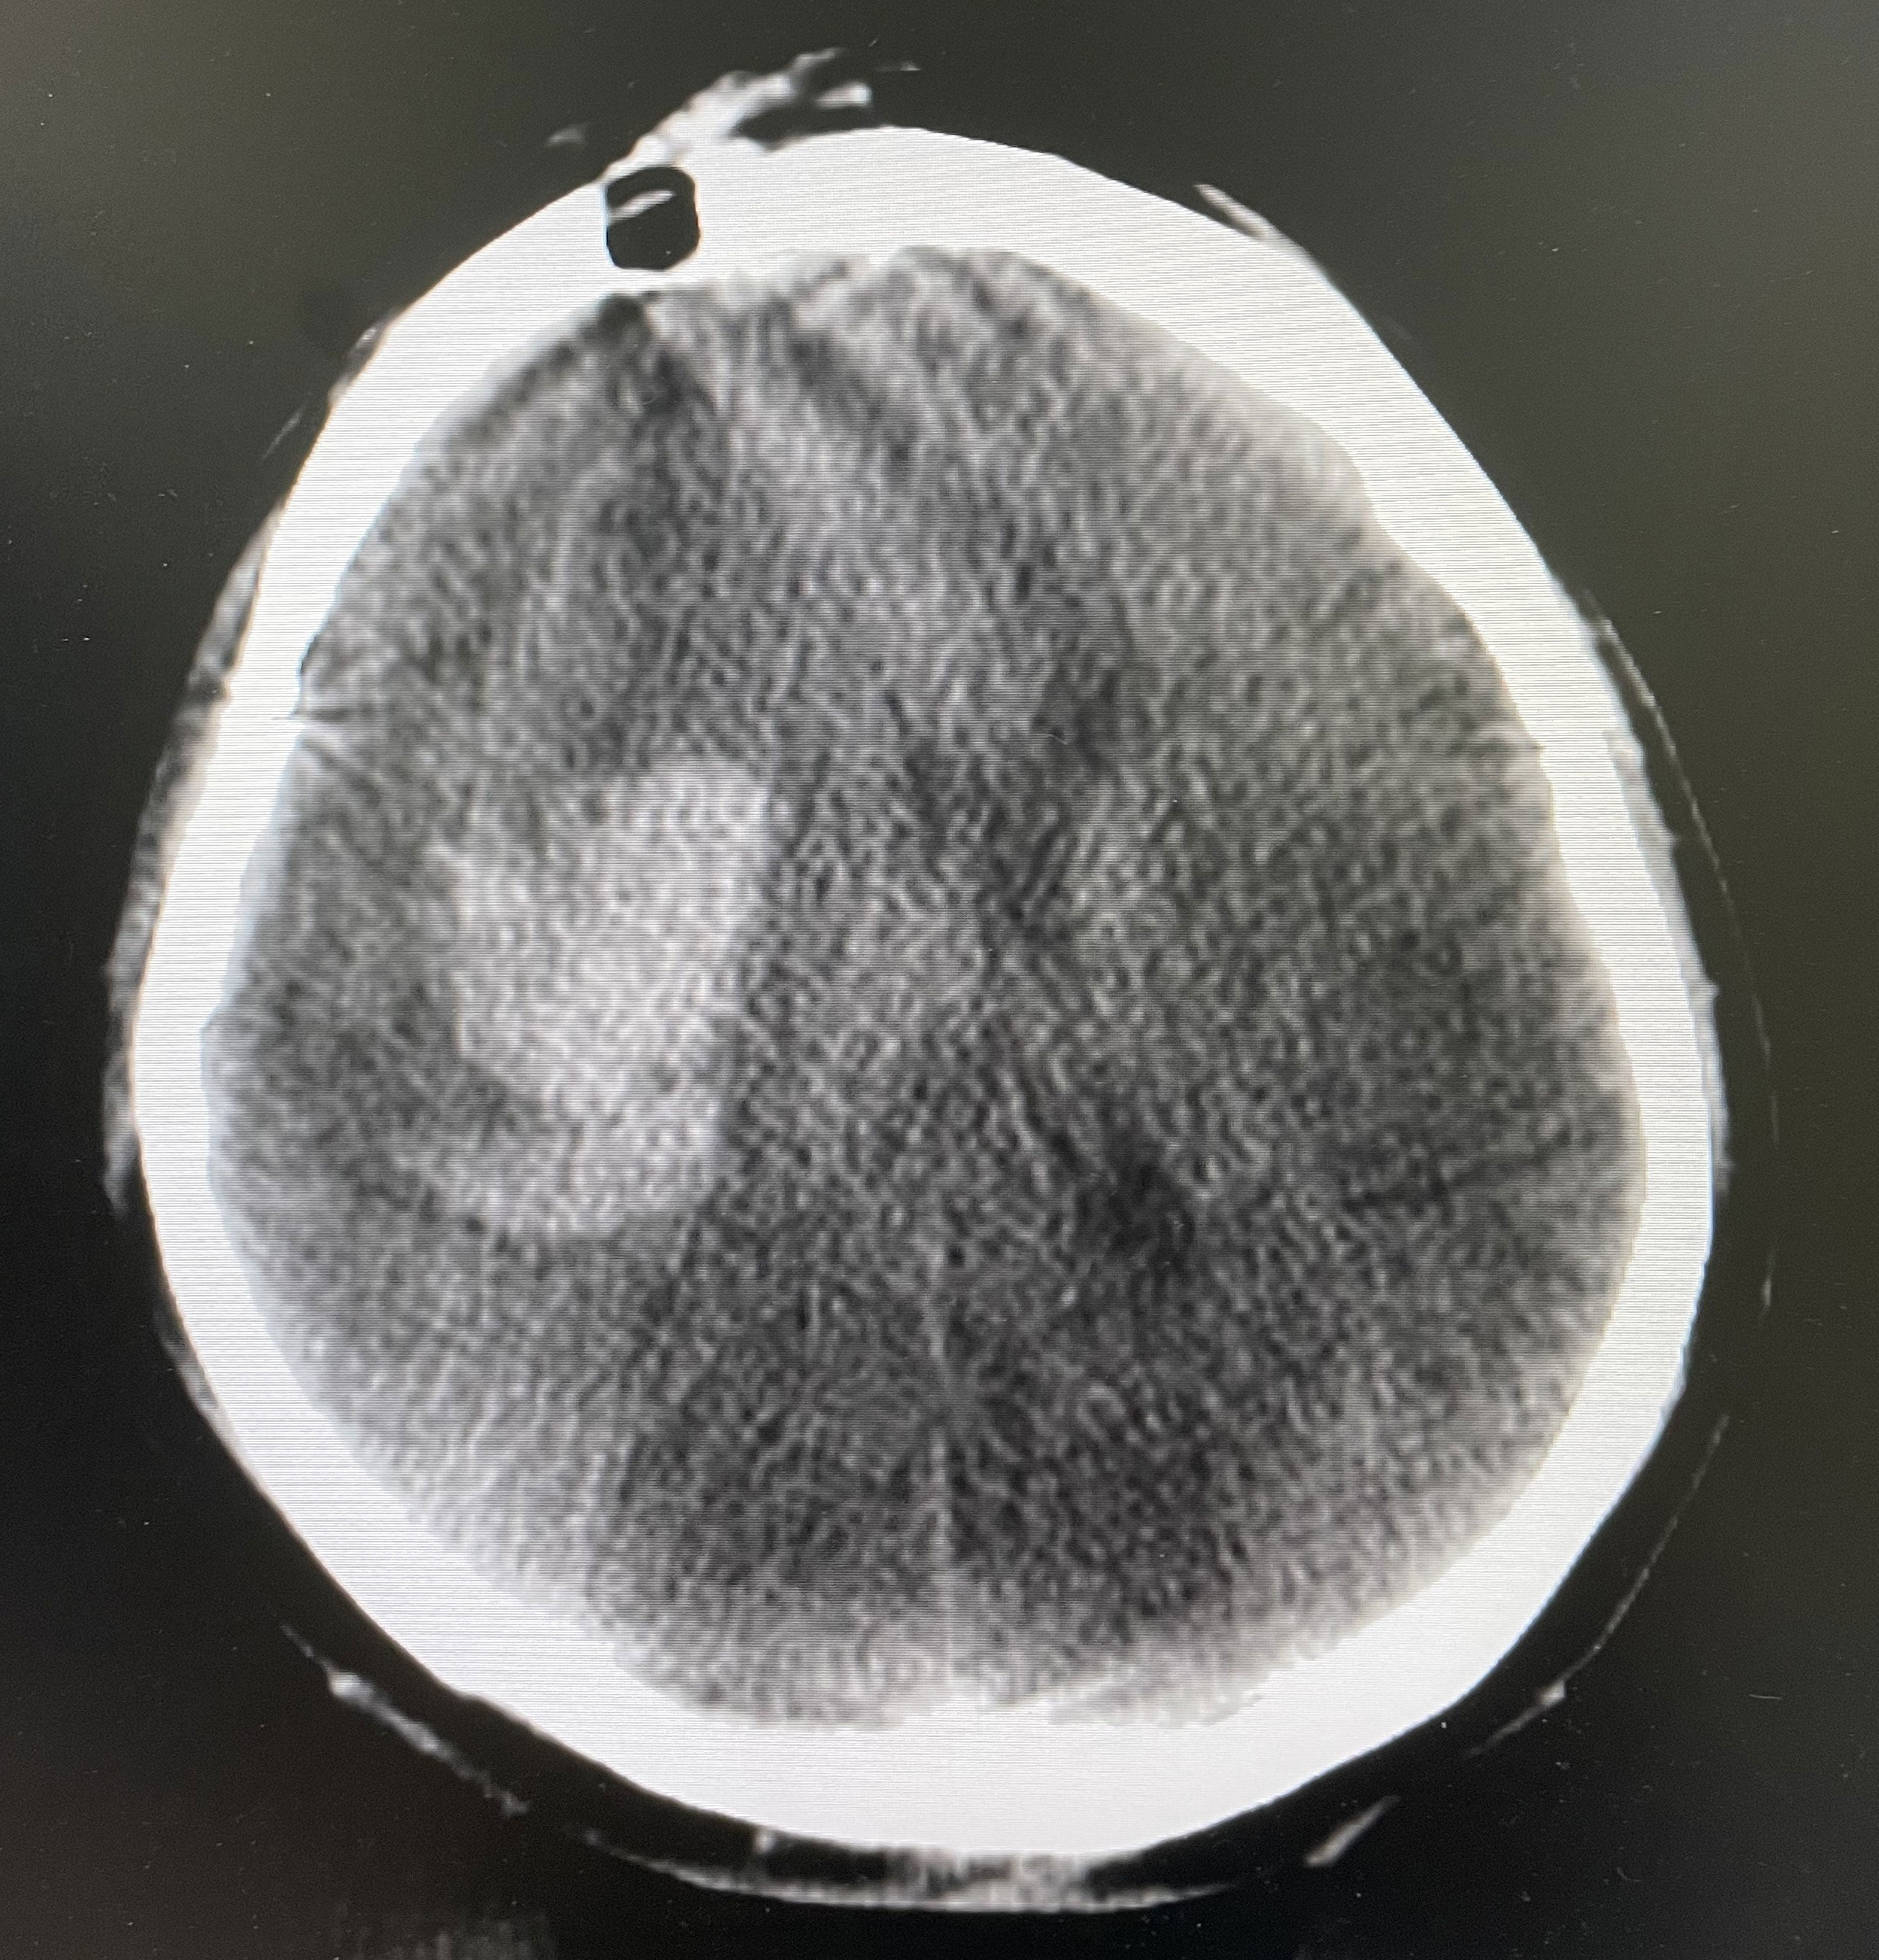

The surgical incision site was marked with a metal object on the forehead, approximately 2 cm from the midline and 3 cm from the orbit on the hematoma side (Figure 2). The priority was to make an incision in the frontal stria and avoid the frontal sinus to prevent cerebrospinal fluid leakage after surgery and ensure an aesthetically pleasing appearance after wound healing. A hole was drilled in the bone at the metal mark (Figure 3). The C-arm CT function of the digital subtraction angiography (DSA) machine was used to collect the original data for processing; display the coronal, sagittal, and axial CT images; mark the center of the hematoma; and set it as the target site for the puncture (Figure 4). The 3D reconstruction of brain tissue was performed using the 3D reconstruction software Xper CT of the DSA machine, and the bone hole displayed in gray scale was adjusted as the puncture point. Subsequently, the 3D stereo image was rotated, overlapping the puncture point and puncture target. The laser emission direction was determined using the principle of “two points and one line,” and the real-time 3D reference image working angle was recorded (Figure 5). The skull was cut along the coinciding point, and the distance between the puncture point and the puncture target was measured as the puncture depth (Figure 6).